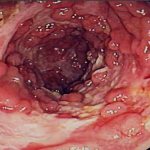

• трофические язвы, особенно с малой тенденцией к заживлению и склонностью к рецидивированию;